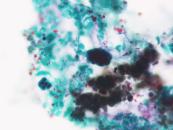

第35回日本臨床細胞学会九州連合会学会(宮崎)スライドカンファレンス症例4

種別:婦人科

出題:熊本大学病院 病理診断科・病理部 佐野直樹 先生

| 年齢 | 60歳代 | 性別 | 女性 |

| 採取部位 | 子宮頸部 | 採取方法 | 擦過 |

| 検体処理法 | 従来法 |

既 往 歴:糖尿病、脂質異常症

現 病 歴:4年前に帯下の増加を自覚し受診し、子宮頸部細胞診でNILMの判定。今回、下腹部痛を主訴に受診し、腟鏡診では病変は不明瞭だったが、双合診で子宮頸部全体に硬結あり。

| 正解 | 5.胃型粘液性癌 |

| 1.化生細胞および修復細胞 | 3件 | (3.1%) | |

| 2.重層性粘液産生上皮内病変(SMILE) | 38件 | (39.2%) | |

| 3.通常型腺癌 | 10件 | (10.3%) | |

| 4.明細胞癌 | 26件 | (26.8%) | |

| 5.胃型粘液性癌 | 20件 | (20.6%) | |

| 投票総数 | 97件 | (100%) |